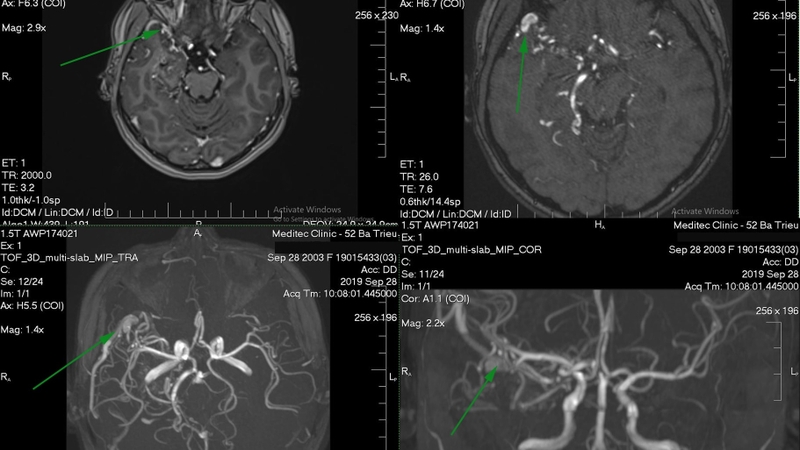

Chụp mạch máu cộng hưởng từ MRA (Magnetic Resonance Angiography) chính là phương pháp đặc biệt hơn của MRI để khảo sát tim với những mạch máu khác trong cơ thể. Đây chính là kỹ thuật an toàn và không sử dụng biện pháp xâm lấn.

Trong quá trình thực hiện, bệnh nhân sẽ được nằm ở trong máy quét hình ảnh cộng hưởng từ. Ở một số trường hợp, bệnh nhân cần phải thực hiện tiêm thuốc tương phản từ đường tĩnh mạch để có thể cho ra hình ảnh rõ nét hơn.

Phương pháp này sẽ cung cấp những hình ảnh có giá trị chẩn đoán cao để xác định rõ về nguồn gốc và chỉ định điều trị phù hợp. Với ưu điểm vượt trội, phương pháp trục này ngày càng được sử dụng phổ biến. Cách chụp MRA để phát hiện các triệu chứng và nguyên nhân bệnh lý như: